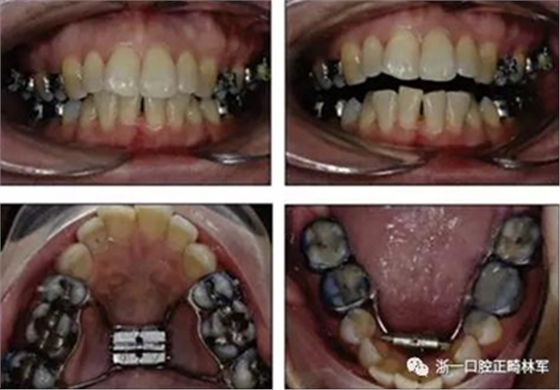

手術(shù)前三周,上、下頜磨牙和前磨牙使用分壓圈進(jìn)行分牙。術(shù)前一天,去除下頜切牙托槽,安裝hyrax擴(kuò)弓器。

全麻下進(jìn)行上頜骨腭中縫骨皮質(zhì)劈開(kāi)及下頜正中劈開(kāi)術(shù)。手術(shù)后,用X光片檢查上頜骨和下頜骨中線(xiàn)切口的位置和方向。

術(shù)后第9天開(kāi)始旋轉(zhuǎn)擴(kuò)弓器,每天轉(zhuǎn)2次,每次轉(zhuǎn)90度,即擴(kuò)開(kāi)0.5mm。每隔1周進(jìn)行檢查,目標(biāo)上頜擴(kuò)開(kāi)9mm,下頜擴(kuò)開(kāi)6mm。18天后,上頜中切牙間出現(xiàn)8mm間隙。下頜出現(xiàn)6mm間隙,(于13天出現(xiàn)后,停止旋轉(zhuǎn)擴(kuò)弓器)。在擴(kuò)弓器旋轉(zhuǎn)3天后,拍片發(fā)現(xiàn)左下頜中切牙遠(yuǎn)中牙根中段有一條低密度陰影,臨床冷熱診反應(yīng)遲鈍,可能為術(shù)中損傷所致。牙體牙髓科會(huì)診,建議行根管治療,故行根管治療。

擴(kuò)弓保持8周后,除擴(kuò)弓器影響牙外粘接托槽,使用0.014鎳鈦絲進(jìn)行排齊、整平。旋轉(zhuǎn)停止后3個(gè)月拆除擴(kuò)弓器,全口粘接托槽,使用0.016niti繼續(xù)排齊整平。佩戴可摘保持器,保持上頜寬度。在使用至0.018x0.018niti7周,徹底排齊整平后,使用大弓型的0.016x0.022不銹鋼絲,繼續(xù)維持原有寬度,同時(shí)停止使用可摘保持器。掛II類(lèi)牽,糾正磨牙關(guān)系,使用鏈圈關(guān)閉散在間隙,少量使用IPR去除局部前牙的黑三角。術(shù)后9個(gè)月拍全景示,牙根平行度可,再無(wú)其他牙根出現(xiàn)問(wèn)題。1年7個(gè)月后治療結(jié)束。上下頜3-3舌側(cè)保持器+哈雷氏保持器進(jìn)行保持。